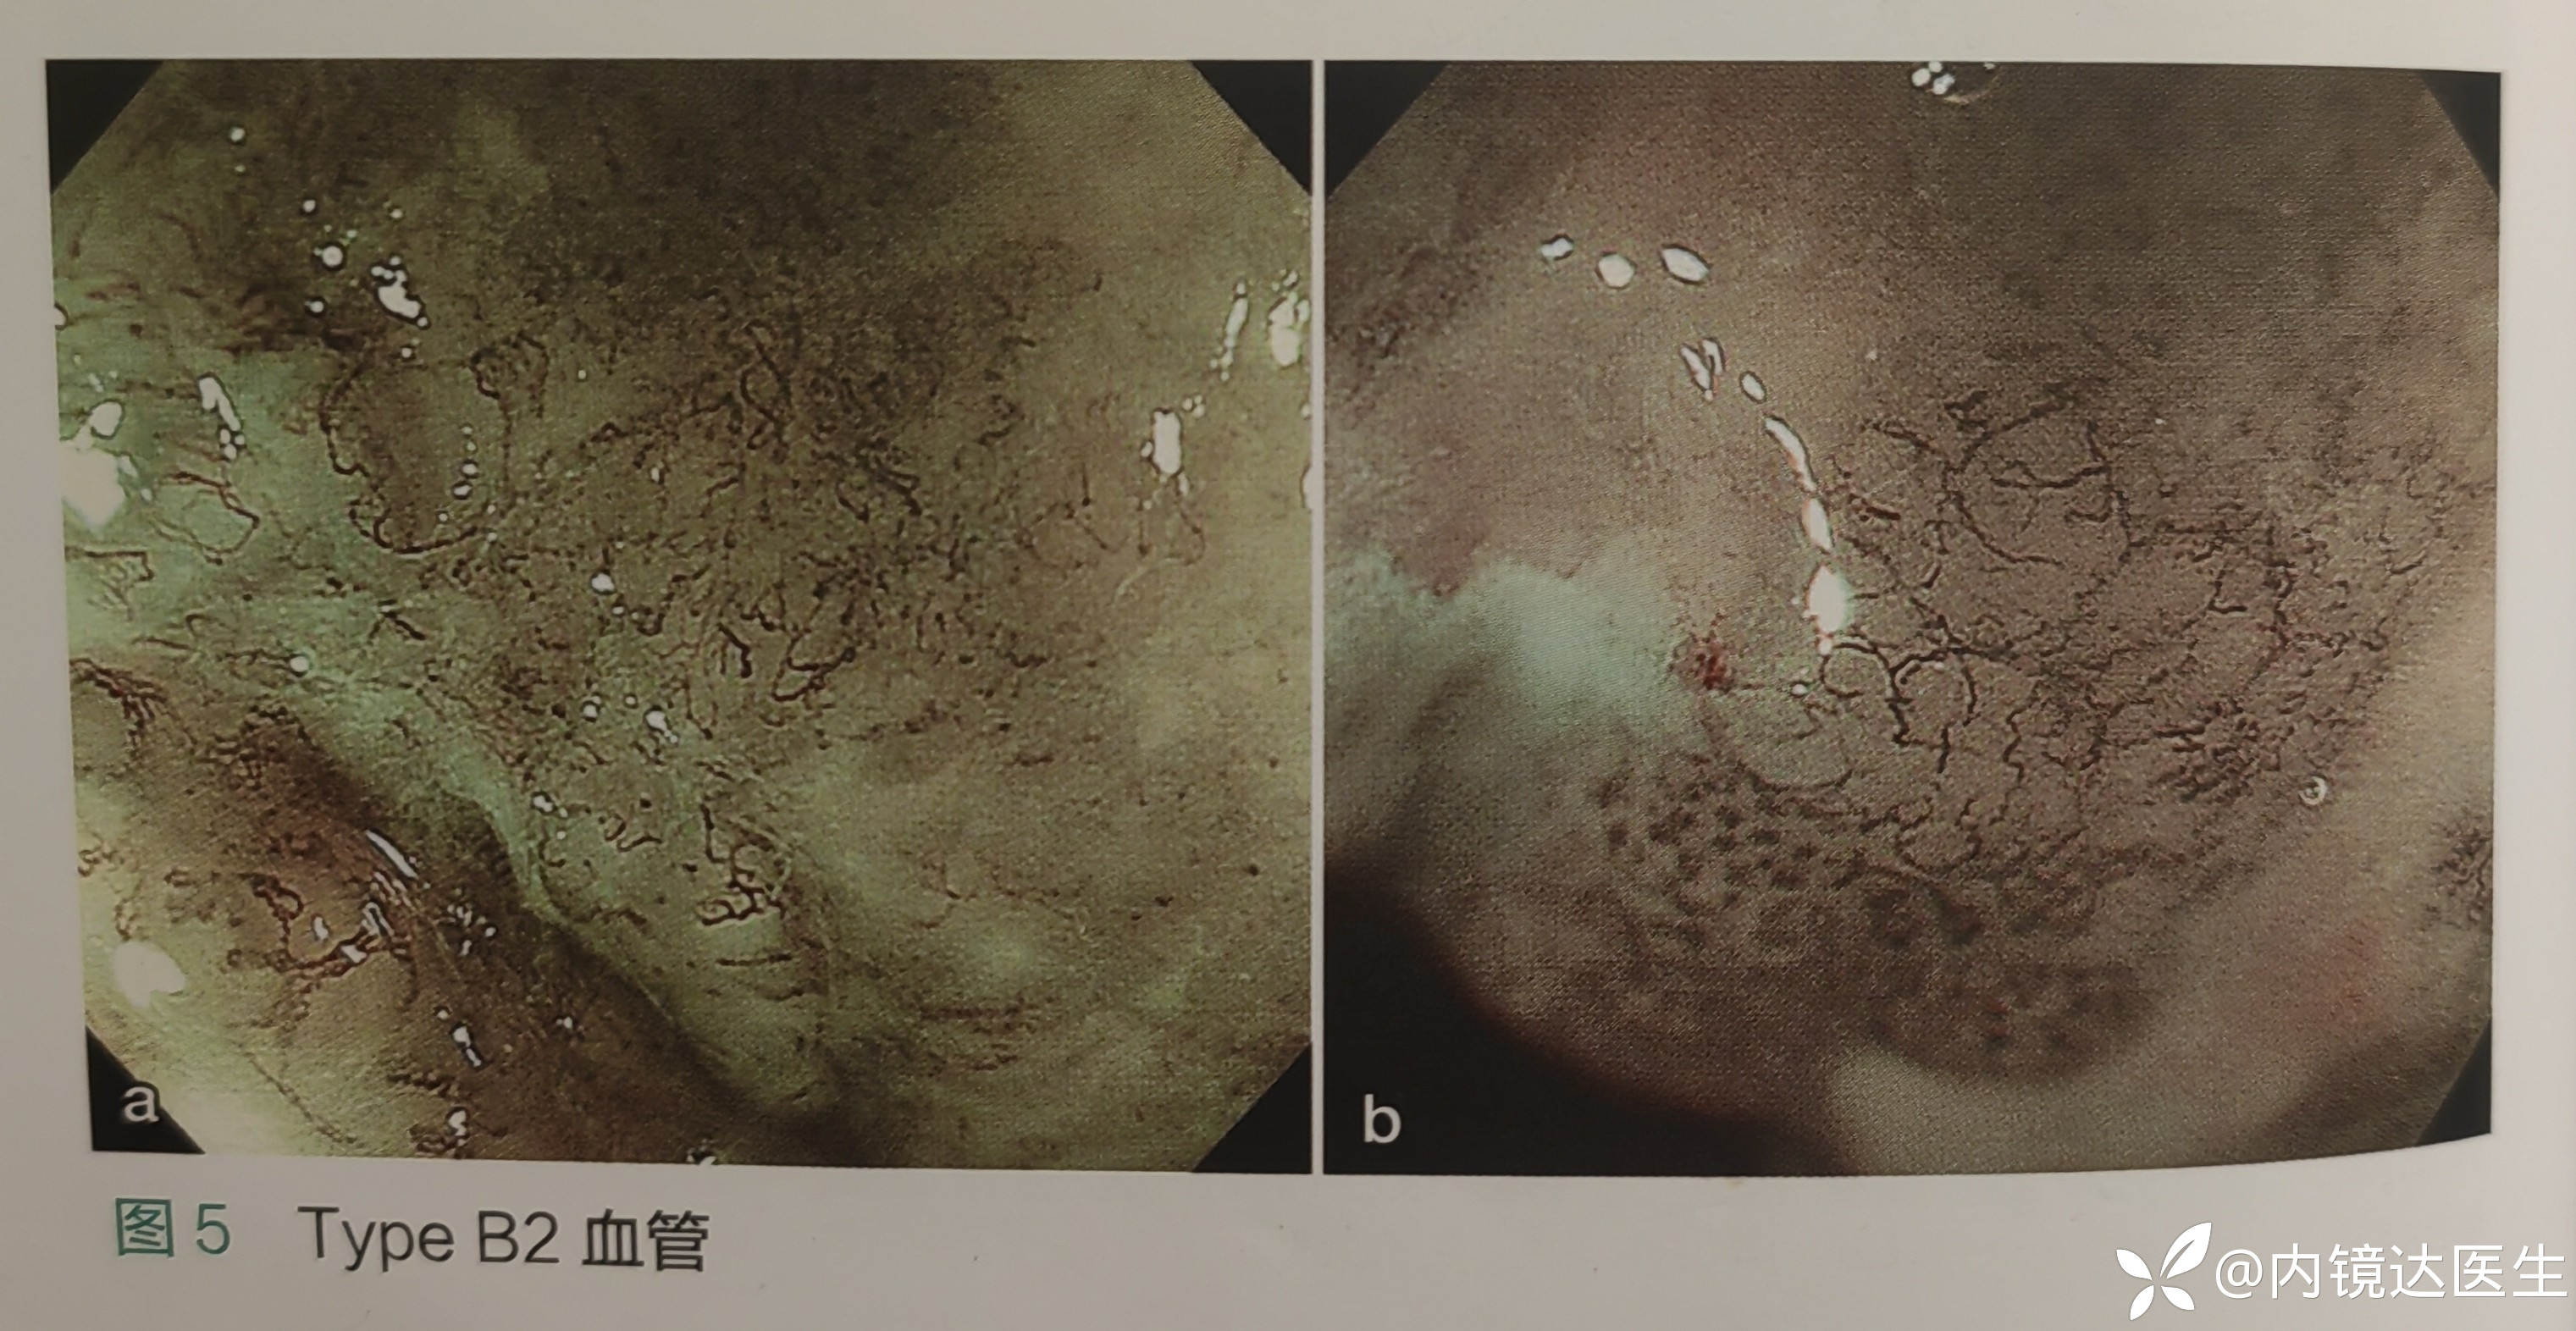

B2 不形成回路的异常血管,提示T1a MM/SM1 ESD的相对适应症 (MM/SM1正确诊断率只有50-70%,还需要结合榻榻米征来进行综合判断)

注:在活检部位和糜烂中出现的类似于B2血管不能用于判断浸润深度。